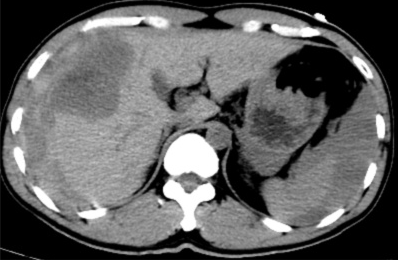

手术顺利,术后患者转正重症医学科给予输血、补液、止痛及康复治疗。术后3天,患者复查血,肝功能正常。后续恢复良好,并在短期内出院。

据悉,患者既往有多年乙型肝炎病史,突发右上腹剧烈疼痛入院。患者入院时血压70/40mmHg,心率110次/分,全腹压痛。血常规血红蛋白87g/L,甲胎蛋白>1210 ng/ml。腹部B超检查及CT平扫检查示“肝肿瘤并出血,腹腔积血积液”。